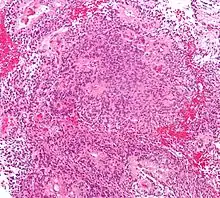

Micrograph of an ependymoma. H&E stain.

Ependymomas are composed of cells with regular, round to oval nuclei. There is a variably dense fibrillary background. Tumor cells may form gland-like round or elongated structures that resemble the embryologic ependymal canal, with long, delicate processes extending into the lumen; more frequently present are perivascular pseudorosettes in which tumor cells are arranged around vessels with an intervening zone consisting of thin ependymal processes directed toward the wall of the vessel.[4]